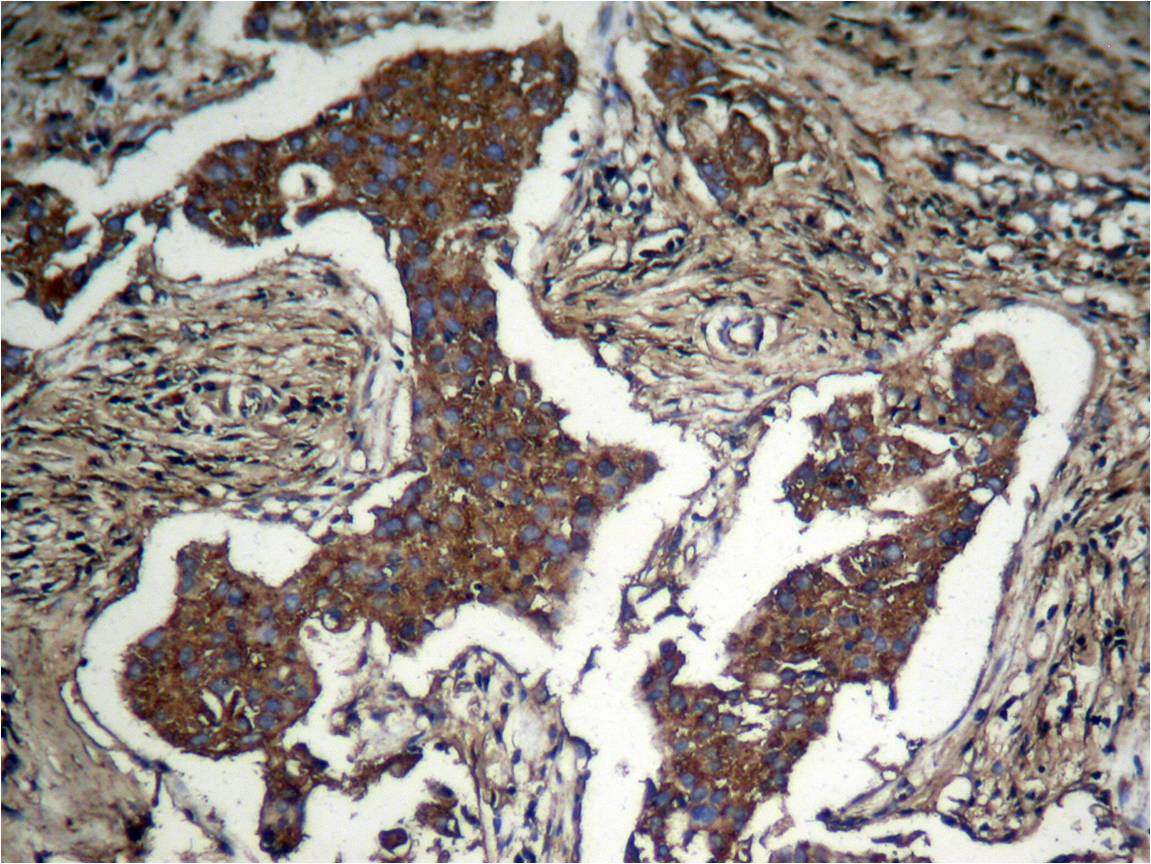

Immunohistochemical analysis of paraffinembeddedhuman Lung carcinoma tissue usingAkt (Phospho-Ser473) Antibody #11054.